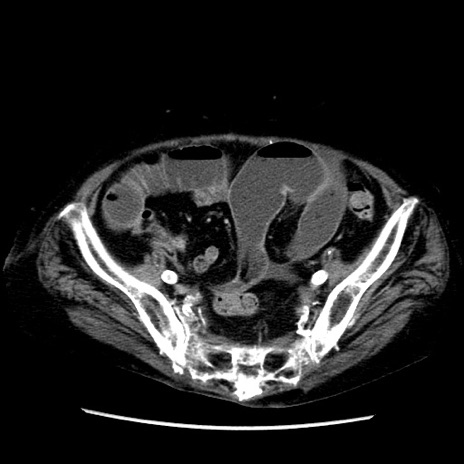

症例14(横断像)

【症例】 90歳代女性

【主訴】 腹痛・嘔吐

【現病歴】今朝から左側腹部痛を認めた。 経過観察していたが、嘔吐を認めたため来院。

【既往歴】 子宮癌術後

【身体所見】 意識清明、BP 127/54mmHg、P 98bpm Sp02 95%(RA)、BT 35.8°C、腹部平坦・軟腸ぜん動音聴取良好、右下腹部圧痛(+) 反跳痛なし

【データ】WBC 9800、CRP 0.46